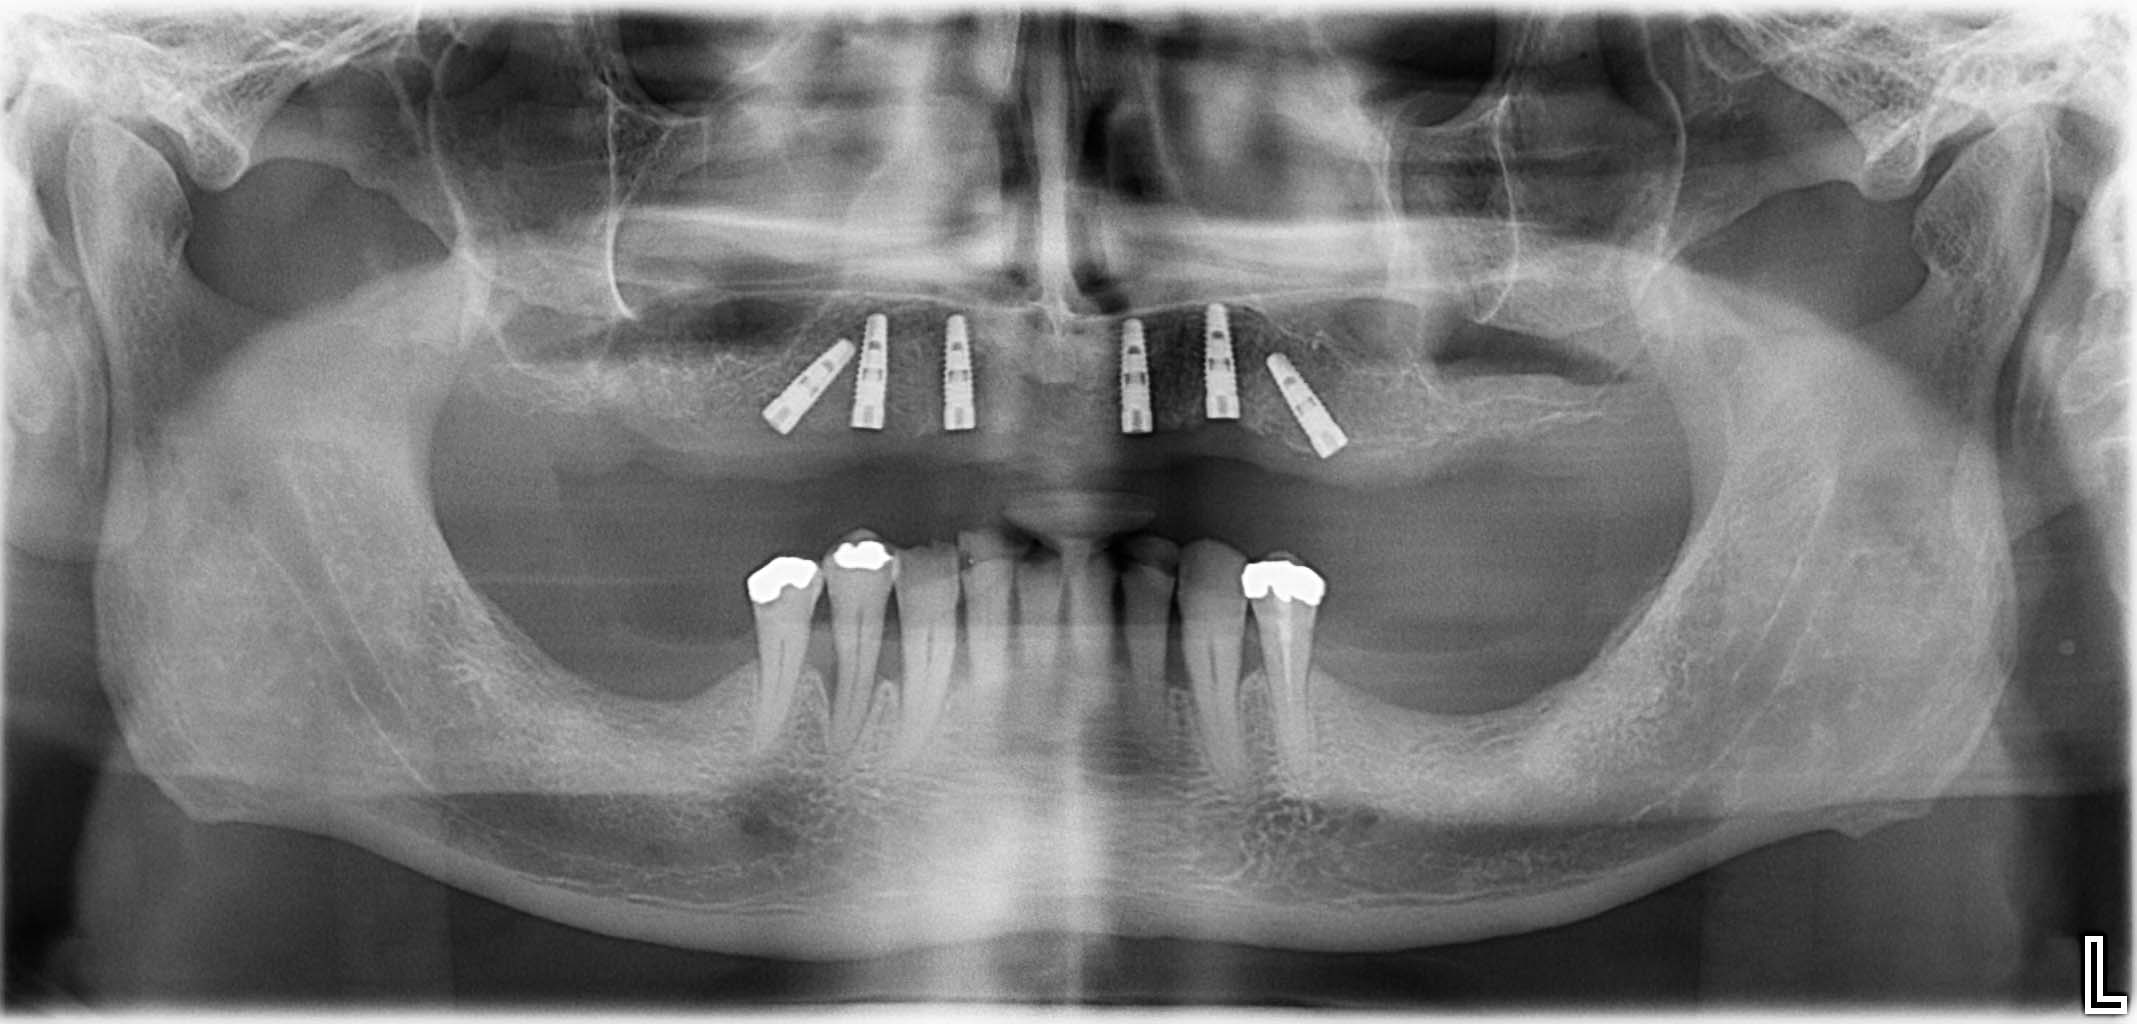

Erfolgreich implantierte Patientenfälle (klinische Fotos)

3D-Ausblick

Mit unserer 3D-Röntgen-Technik sehen Sie Ihr Ergebnis schon vorab! So wissen Sie immer, worauf Sie hinarbeiten.